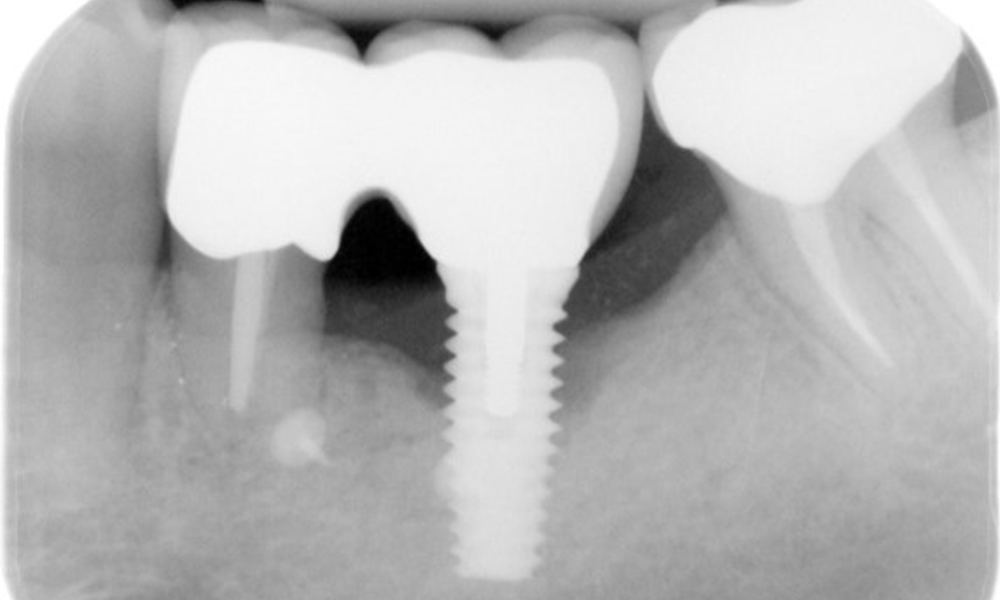

A 52-year-old patient presents at a preventive care session. The patient has no systemic disease and is not taking any medication. He has had various dental treatments and also has two active carious lesions. In addition, the patient has four implants (2nd, 3rd and 4th quadrants). He is revealed to have early periodontal disease (stage IV, grade B). His periodontal condition is stable; a probing depth of Probing depths (ST) of 5 mm is only evident at the implant in region 36. Gingivitis is also identified.

The patient has no particular risk factors with specific dental implications in his medical history. The key factor, therefore, is the requirement in terms of oral health. In this respect, there is evidence of a probing depth of 5 mm at the implant in the 3rd quadrant and, on the X-ray image, increased bone loss. The patient also has currently stable early periodontal disease and two active initial carious lesions.